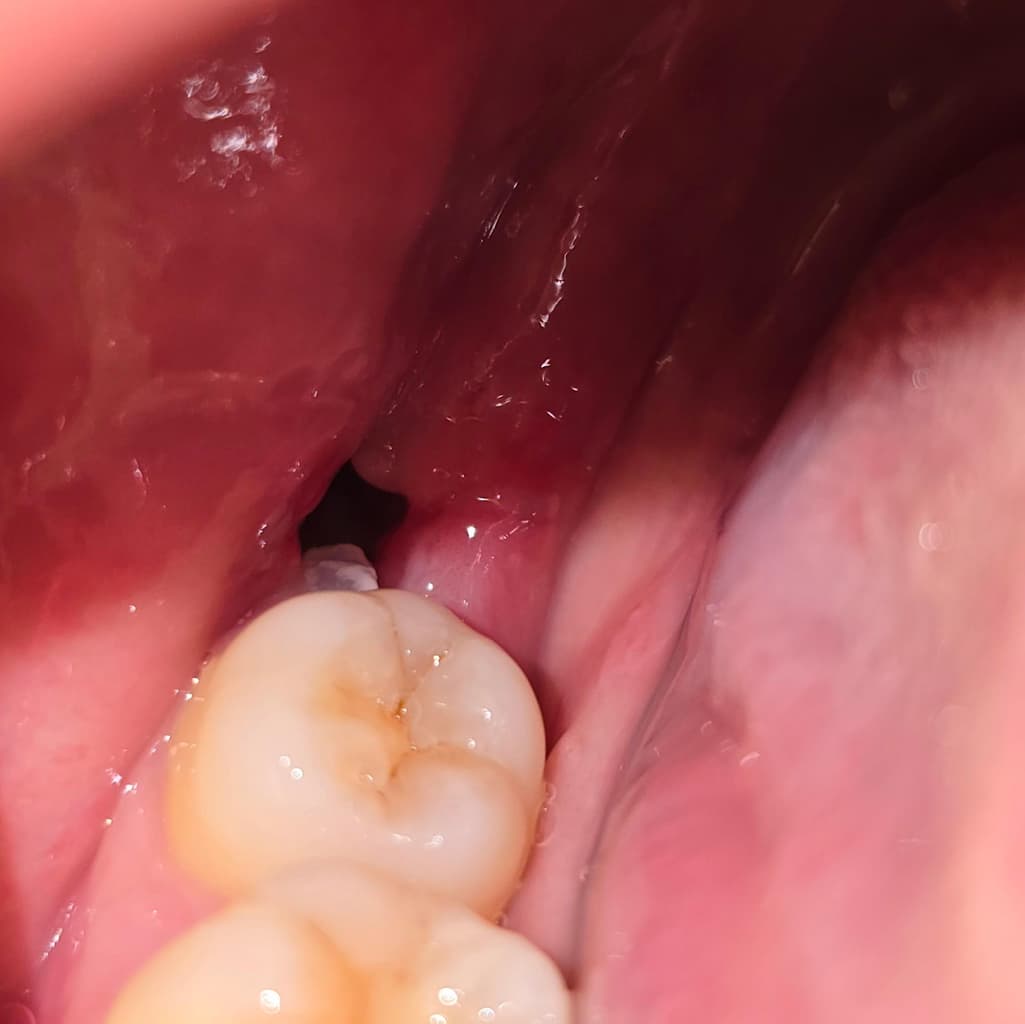

일주일 전에 사랑니 뽑고 어제 실밥도 제거했는데요 오늘 저녁 먹고 보니까 쌀알 같은 게 보여서요 가글을 해도 안 빠지고 혀로 건드리면 요리조리 움직여지기만 해요 아프거나 하지도 않고 좀 딱딱한 것 같기는 한데 단순히 쌀알이 낀 걸까요? 당장은 그냥 둬도 괜찮나요?

사랑니를 발치하고 해당 부위에 이물질이 들어가게 되면 사진처럼 보일 수 있습니다. 가볍게 가글을 하면서 빼보는 것이 좋으며 억지로 빼려고 하지 않는 것이 좋습니다. 사랑니에 있는 이물질을 억지로 빼려고 하면 출혈이 될 수 있기 때문입니다.